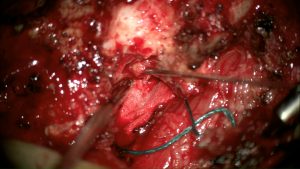

Abordaje longitudinal con esqueletización L2-L4 derecha; disección del componente extracanal del tumor; se aprecia relación con apófisis transversa L3 derecha

Tras exéresis de la apófisis transversa L3

En esta imagen, medial es superior

Prefiero resecar de fuera a adentro; en la imagen se aprecia detalle de la raíz tras artrectomía parcial que marca límite medial del tumor, (por lo que se evita exponer más contenido intradural del canal y, en la mayoría de casos, sin salida de LCR).

Tras exéresis tumor procedemos a revisar muñón proximal; en caso de no apreciar morfología radicular o seguir el tumor un crecimiento hacia el espacio subaracnoideo, completaría exéresis hueso (para y lamina/s) y apertura dural.